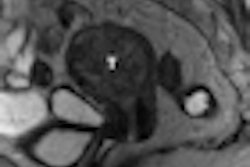

| Top image is of a 47-year-old man with early relapse after complete remission, with relapse-free survival of 179 days. High value for peak is 0.71 and Kep is 0.022. Bottom image is of a 62-year-old woman with low value for peak (0.15) and Kep (0.0024), who remained in remission until November 2009 and had relapse-free survival of 1,674 days. Images courtesy of Radiology. |

In their analysis, Chen and colleagues found that high values of peak (≥ 0.42), slope (≥ 0.0235), amplitude (≥ 0.03), and Kep (≥ 0.0082) were associated with shorter overall survival (p = 0.004, 0.01, 0.034, and 0.026, respectively). A high value of Kep also was associated with shorter relapse-free survival.

The cutoffs for high and low values for DCE-MRI pharmacokinetic parameters in patients at complete remission status were set as 0.42 for peak, 0.0235 for slope, 0.03 for amplitude, 0.0082 for Kep, and 0.0975 for Kel.